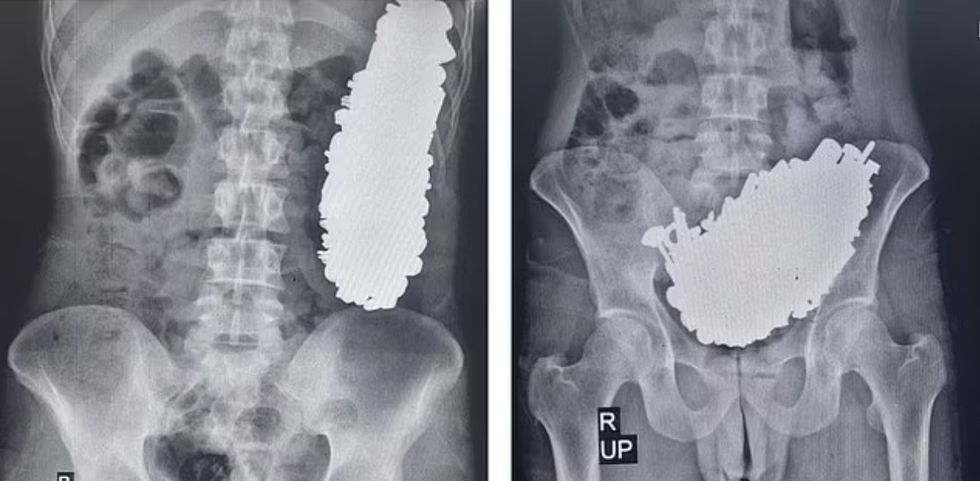

Rëntgenografitë befasuese tregojnë masën e metalit që bllokon daljen e stomakut të burrit, gjë që i shkaktonte dhimbje kronike në stomak dhe të vjella të shpeshta që e lanë atë të paaftë për të ngrënë apo pirë.

Mjekët e futën burrin në sallën e operacionit dhe, nëpërmjet një prerjeje në stomak, nxorën gjithsej 452 'vida, arra, çelësa, gurë dhe pjesë të tjera metalike' me peshë 2.9 kilogramë. /Telegrafi/